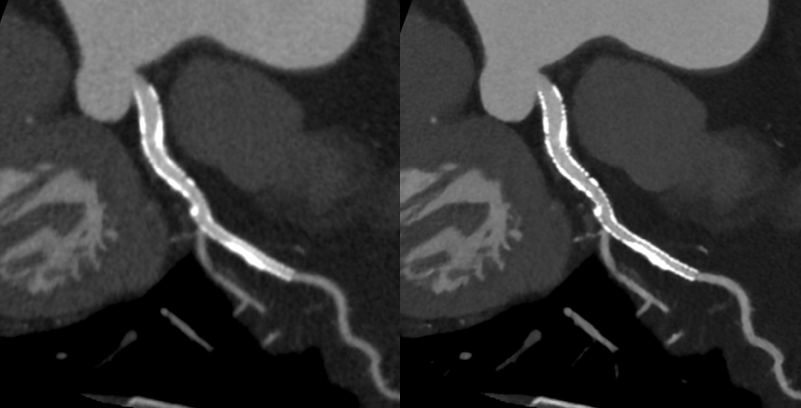

キヤノンメディカルシステムズが開発したPrecise IQ Engine(PIQE)によるディープラーニングの画像によって、冠動脈CT検査で評価が難しい石灰化やステントに接する部分の描出が向上されるため、さらに正確な画像診断が可能となりました。

石灰化症例:左の従来画像と比較して、右の高精細ディープラーニング画像では血管周囲の白い石灰化部分がシャープに描出されています。

ステント症例:左の従来画像と比較して,右の高精細ディープラーニング画像では小さなステントの内部も明瞭に描出されています。